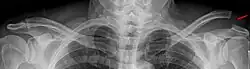

L'épaule (nom féminin) est la région morphologique se situant à la jonction du tronc avec le membre supérieur.

L'épaule comporte 2 articulations qui fonctionnent de concert et qui concourent à en faire le complexe articulaire le plus mobile du corps humain. Elle permet d'orienter le membre supérieur dans l'espace, autorisant en particulier son extrémité effectrice, la main, à assurer ses rôles de préhension et de communication avec l'environnement situé à sa portée.

Anatomie descriptive

A : ligament acromio-claviculaire. B : acromion. C : ligament coraco-acromial. D : ligament coraco-huméral. E : tendon du long chef du biceps. F : tubercule mineur de l'humérus, ou trochin. G : capsule ligamentaire. H : processus coracoïde. I : ligament coraco-claviculaire (comportant le trapézoïde et conoïde). J : clavicule. K : tubercule majeur, ou trochiter

Le complexe articulaire de l'épaule met en relation quatre os :

- le manubrium sternal (ainsi que le premier cartilage costal) ;

- la clavicule ;

- l'omoplate (scapula) ;

- la tête humérale.